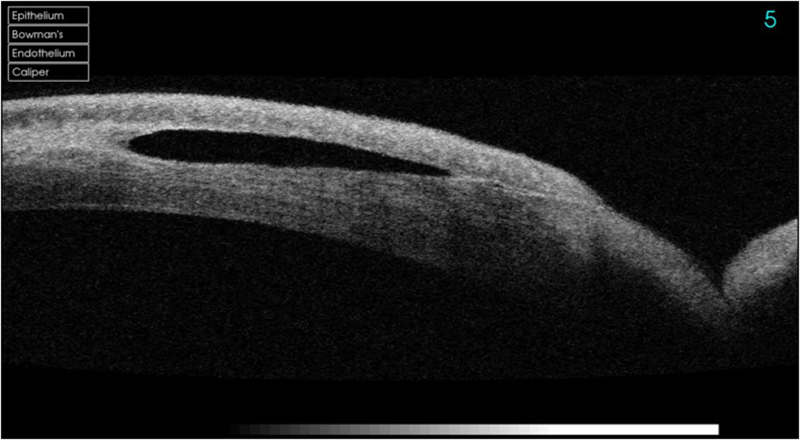

ALK: Queratoplastia lamelar anterior (“anterior lamellarkeratoplasty”), se trasplanta la cornea más superficial (<300 micras) (Figura 5).

Figura 5. Queratoplastia lamelar anterior.